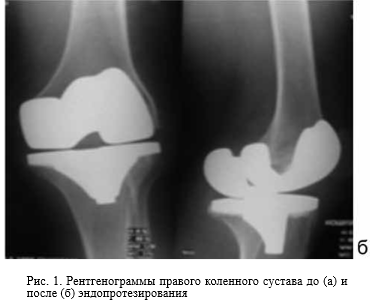

Реконверсия костей

Реконверсия костей 119 фото